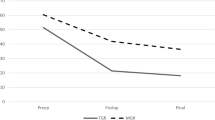

For the axial plane, the apical vertebral rotation also had its largest change in the initial rod implantation without significant changes following subsequent distractions (Fig. 2) despite increasing body height. There was minimal change overall in the rotational profiles, even after rod exchanges. For the thoracic apex, which had the largest changes, besides the initial surgery, the maximum mean change was only 3.4 ± 3.5° thereafter. Similarly, the lumbar apex and proximal thoracic apex had maximal mean changes of 4.3 ± 6.8° and 3.4 ± 3.5°, respectively. Further analyses performed comparing the three parameters showed no significant correlations between coronal, sagittal and axial plane changes except for changes in coronal parameters and T1–L12 kyphosis and L1–L5 lordosis (Table 5).